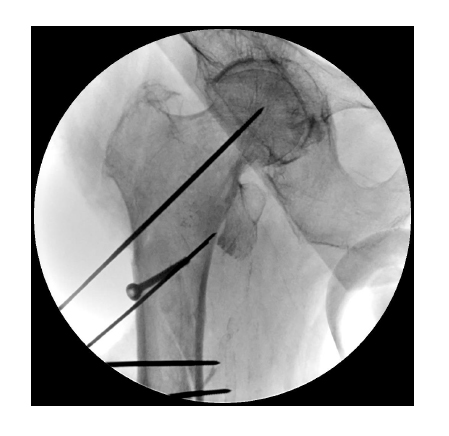

The Company’s product portfolio includes a wide range of mobile C-arm systems of different power for X-ray guided surgery, minimally invasive surgery and interventions for patients with various disorders, e.g. in orthopedics and traumatology, abdominal surgery, urology and gynecology, vascular surgery, and cardiac surgery practice.

A wide range of C-arm movement in all directions including motorized 180° turn in combination with the possibility to move the system throughout the length and breadth of the table without turning the base makes positioning more comfortable and leaves more space for a surgeon. Motorized movements of flat panel detector around its axis without imaging quality loss allows increasing the coverage of the zone of interest thereby enhancing the image information content.